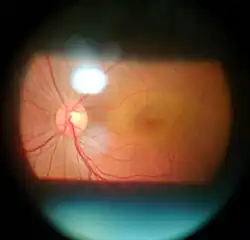

- Retina examination